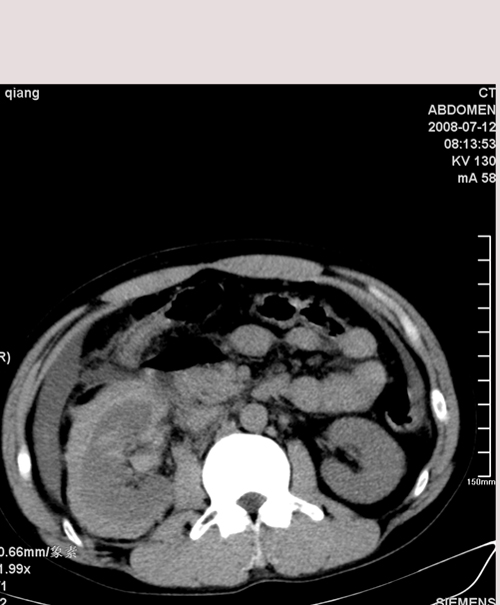

以下是引用muzi888在2008-7-15 10:45:00的发言:[br]大量腹腔积液,气腹,肾皮质弧形高密度影,诊断;1 空腔脏器穿孔 2 右肾包膜下血肿

以下是引用随光逐影在2008-7-15 11:18:00的发言:[br]考虑为:1)腹部空腔脏器穿孔。2)右肾破裂并肾包膜下血肿,肾盂积血。3)腹水(血)。